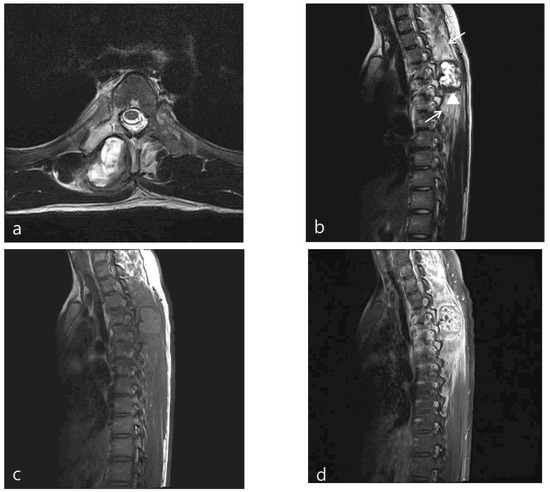

Chest X-ray images showed a radiopaque mass with rim calcification at the T4/5 paraspinal area (Figure 2). Computed tomography images revealed an approximately 2.8 × 2.5 cm wide, 4.5 cm high oval-shaped mass in the right paraspinal muscle with peripheral rim calcification (Figure 2) that was not seen on computed tomography images 5 months prior. The cleft between the mass and the adjacent bone was visible. On magnetic resonance imaging (MRI), the mass showed a heterogeneous high signal intensity on T2WI, isointense to muscle on T1WI with a peripheral low signal intensity rim, and homogeneous enhancement. In addition, perilesional soft tissue edema at the adjacent muscle was also noted (Figure 3). With a history of suspicious trauma (extracorporeal shock wave therapy) and radiologic findings, myositis ossificans was the most suspected diagnosis.

Figure 3. Axial (a) and sagittal (b) T2-weighted MR images show heterogeneous high SI mass in the right paraspinal area between the spinous and right transverse process of T4,5. The calcified rim (arrowhead) is shown as low SI on T2- and T1-weighted images and extensive peritumoral edema (arrows) was also noted. The mass show iso-SI on the T1-weighted image (c). On an enhanced (d) axial image, the mass shows heterogeneous enhancement.